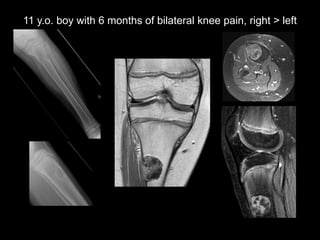

This document discusses 4 unknown pediatric radiology cases presented by Dr. Kirsten Ecklund from Boston Children's Hospital. Case 1 involves a 7 year old boy with fatigue, knee pain and swelling. Case 2 is a 15 year old African American male with cough, shortness of breath and 10 pound weight loss. Case 3 is an 8 year old boy with abdominal pain, distention and vomiting. Case 4 is an 11 year old boy with 6 months of bilateral knee pain greater on the right side.